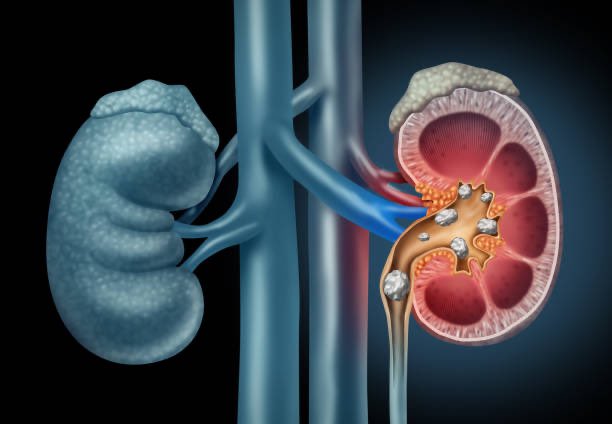

حصى الكلى

تسبب الحصوات الكلوية آلاماً حادة في المجاري البولية، تجعل المريض يئن ويصرخ من شدة الألم، وتحتاج إلى عمل جراحي لإخراجها.